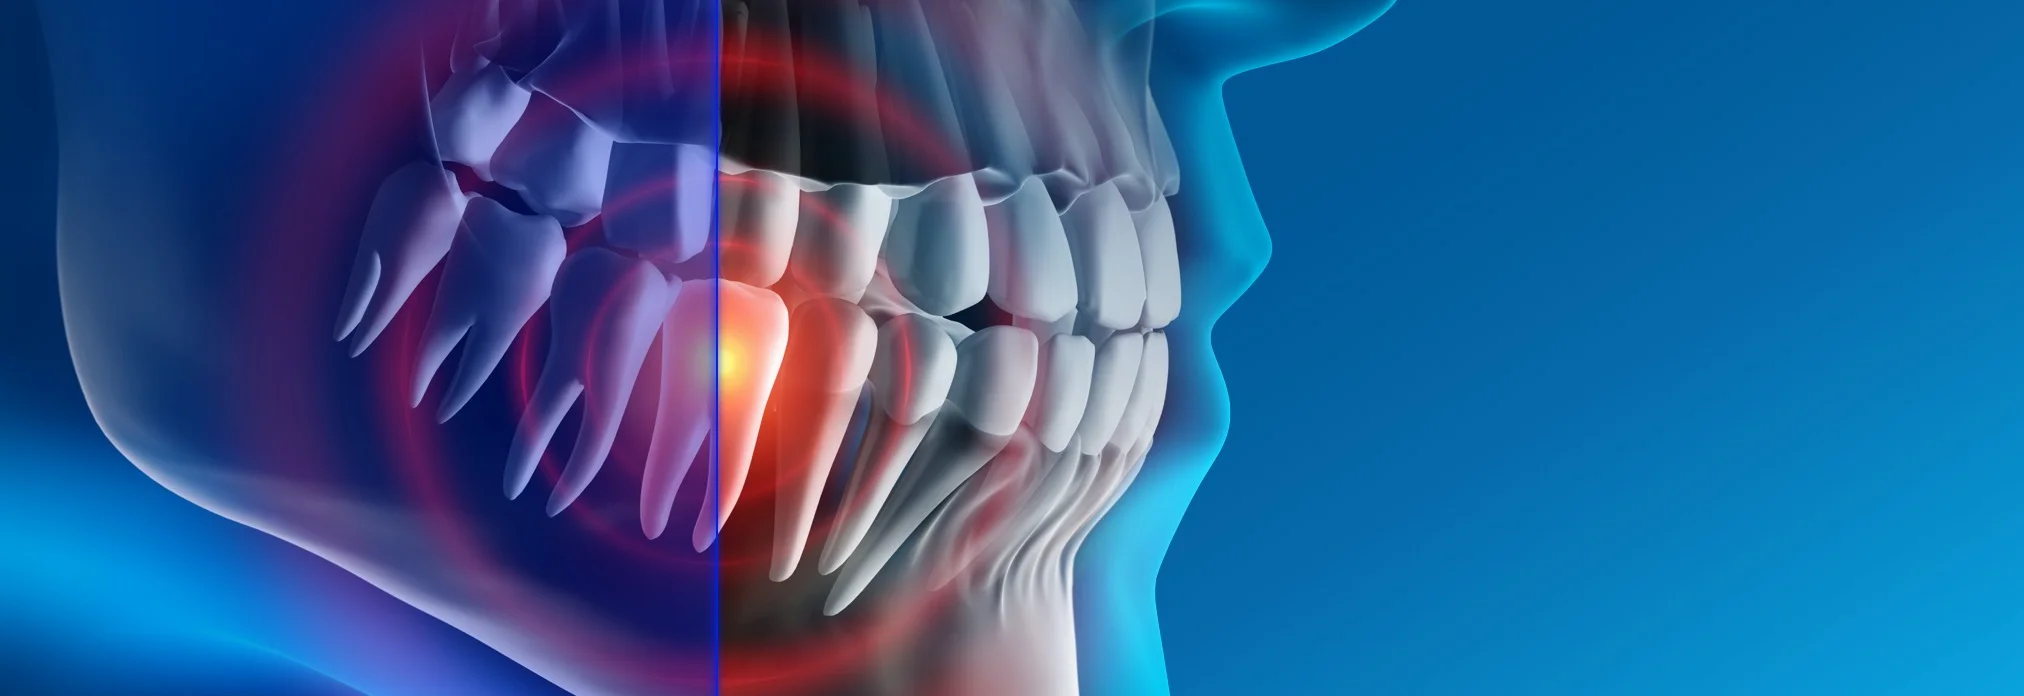

Искусственный интеллект и 3D снимки

3D снимки — это новый уровень диагностики. Но при их появлении возникла достаточно большая сложность.

Дело в том, что 3D снимки гораздо более информативны, чем 2D снимки, но на их чтение требуется гораздо больше времени и более высокая квалификация стоматолога, это гораздо более трудоемкий процесс.

Далеко не каждый стоматолог, умеет правильно читать КТ снимки, для этого требуется отдельное обучение. Также стоматологам не хватало времени выделяемого на прием, чтобы проанализировать каждый зуб.

Что привело к тому, что комплексность диагностики начала страдать. Врачи успевали проанализировать только 1-2 зуба за прием.

Для решения этих проблем была создана Российская разработка, работающая на основе искусственного интеллекта.